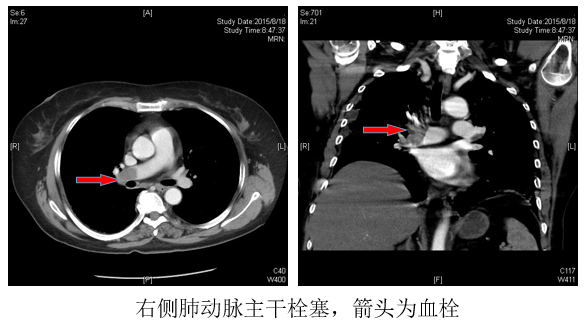

几周前患者工作时不慎摔倒导致髌骨骨折,右下肢石膏固定,卧床制动。骨折的疼痛让患者痛苦不堪,不仅如此,患者开始出现胸痛、喘憋等症状,难道是冠心病?然而来院检查后并未发现心脏问题,结合患者骨折卧床制动的情况医生怀疑为肺栓塞,肺动脉CT成像后果然发现右肺动脉主干栓塞。经由下肢静脉彩超发现患者骨折右腿下肢静脉血栓形成,最终确诊为下肢静脉血栓脱落导致的肺栓塞,如果仍有血栓脱落,将可能出现致命性的后果。并且,肺栓塞若处理不及时还将导致日后肺动脉高压,出现活动后喘憋的症状,严重影响患者生活质量。

血管外科团队针对本例急性肺栓塞患者制定了机械抽栓+植入下腔静脉滤器的治疗方案,利用碎栓取栓装置经皮肤穿刺点通过髂静脉、下腔静脉、右心进入肺动脉,将血栓打碎的同时将血栓抽吸出来。机械抽栓技术治疗急性肺动脉栓塞能够在微创条件下有效清除血栓,避免大剂量溶栓增加的出血风险的同时,快速开通堵塞的肺动脉,结合小剂量局部溶栓,改善患者呼吸困难的症状,挽救患者生命,提高生活质量。由于患者仍存在下肢深静脉血栓,在抽吸肺动脉血栓后下腔静脉放置滤器,预防再次肺栓塞的发生。手术顺利完成,患者肺动脉血栓大部分被抽出,喘憋、胸痛症状明显缓解,患者转危为安。